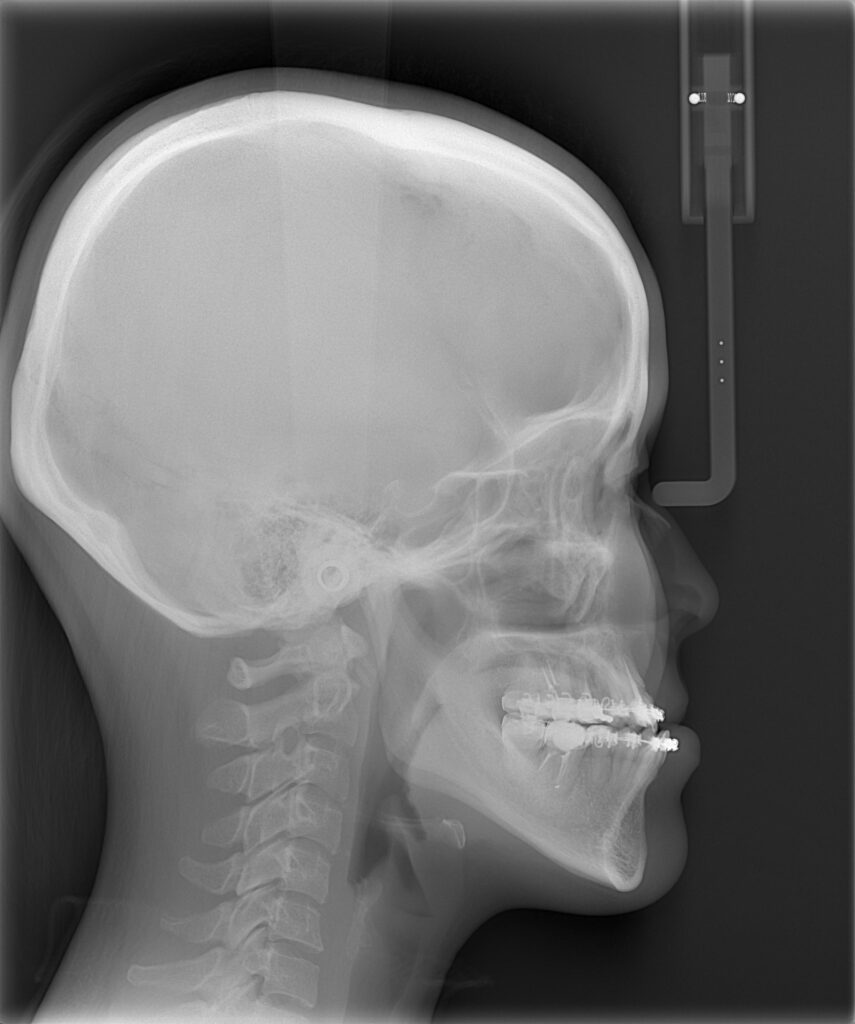

レントゲンを用いて骨格の特徴を把握します。白線の輪郭は標準的な骨格を表しています。標準骨格と比べると、下顎が前に出ていて、なおかつ垂直方向に長いことがわかりました。

ほぼ予定通りの手術が行われました。